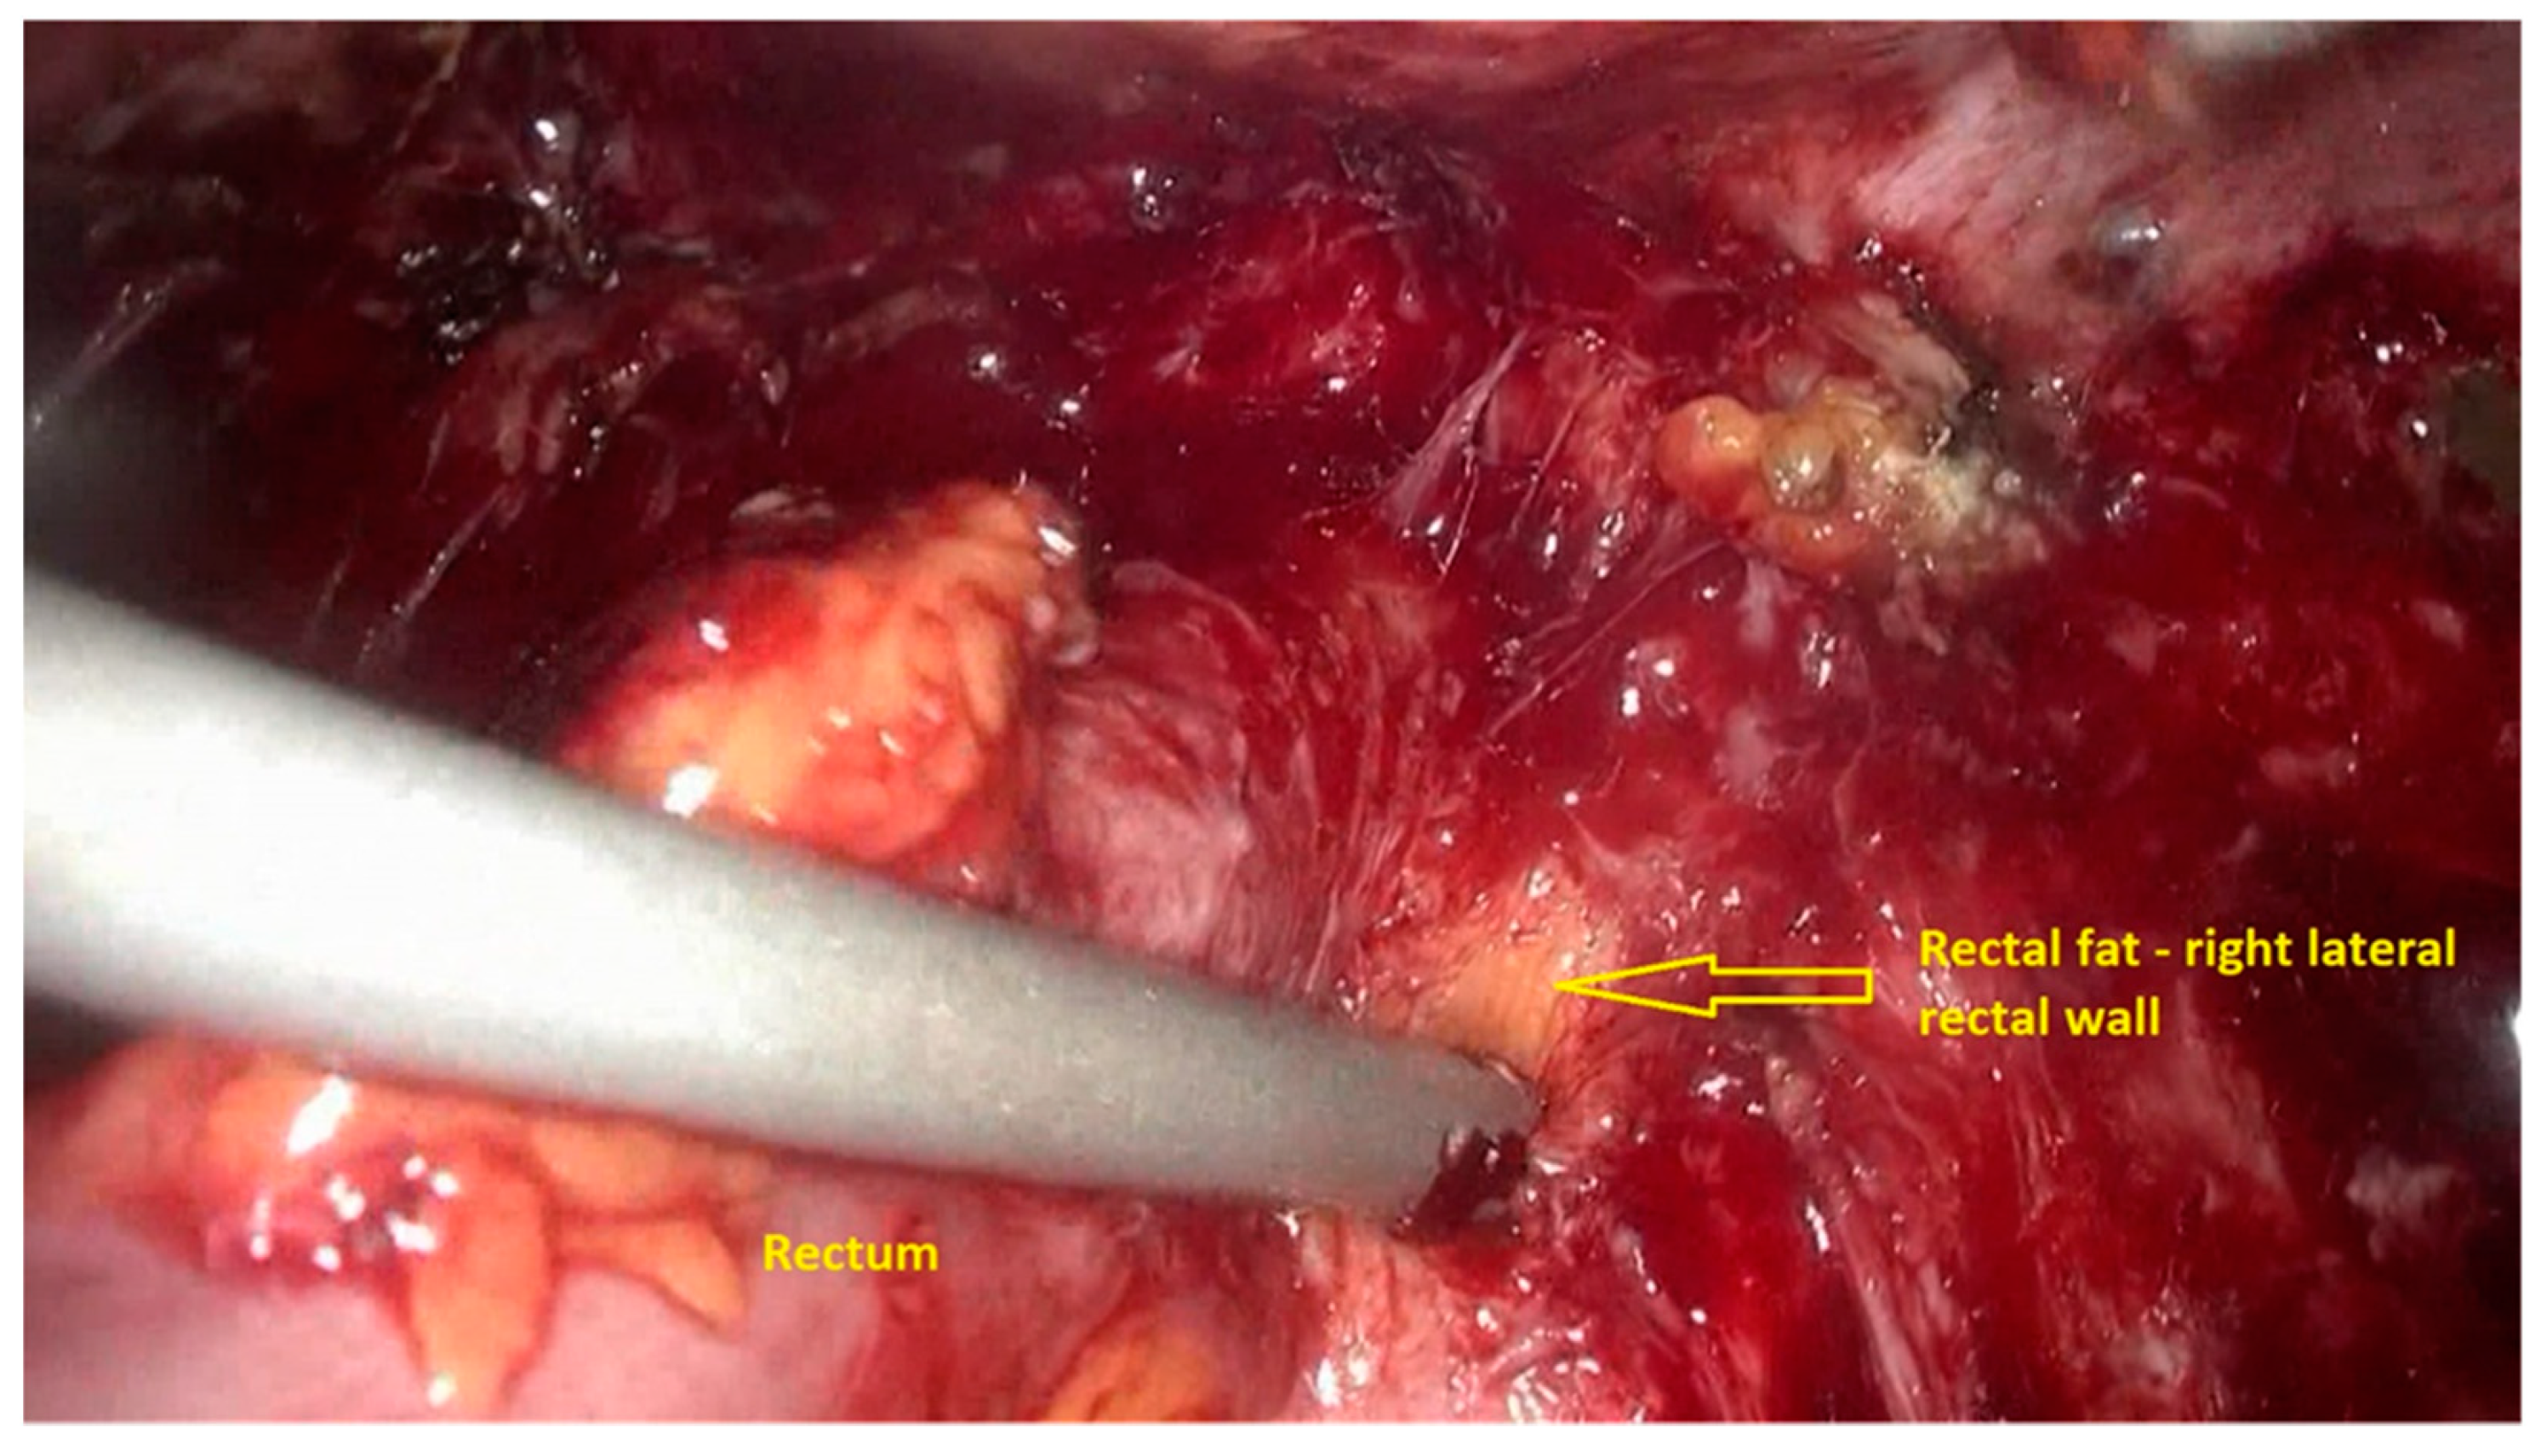

- The deep rectal spaces and rectovaginal septum surrounding the rectal nodule are opened in an anterolateral plan while staying connected to the levator ani muscle and with the preservation of fascia recti (Figure 3).